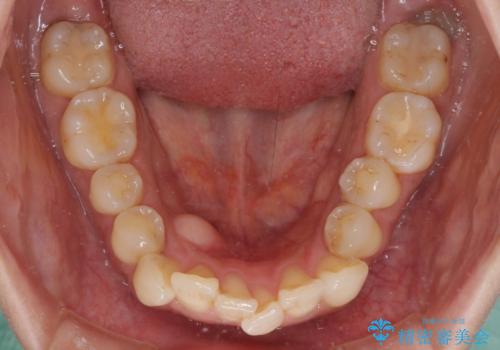

- 全体的なデコボコと、以前抜歯した歯のスペースを閉じた部分が気になるとのことで来院された患者様です。

左上第一大臼歯を抜歯した際に、スペースを閉じたそうですが、歯が傾斜してものが挟まって不快とのことでした。

インビザライン矯正で全体の歯列と整えるとともに、左上第一大臼歯部にはスペースを作り、インプラントによる補綴治療を行うこととしました。

歯の傾斜が改善され、インプラントによるクラウンが装着されたことで、物が挟まることもなくなりました。